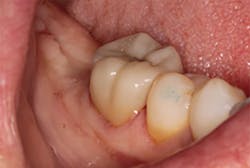

The next day, a good case opportunity presented itself. I had to prepare and scan No. 13 for a crown. I figured it was anteriorly positioned enough that I could test the esthetics, but it was posterior enough that the stakes weren’t too high. Nevertheless, you can see from Figures 1a–1c that we were thrilled with the results. Additional restoration examples can be seen in Figures 2 and 3.

Figures 1a–1c:

1a: Prepared No. 13, 1b: True Definition scan merged with clinical photo, 1c: No. 13 with Lava Esthetic full contour zirconia crown